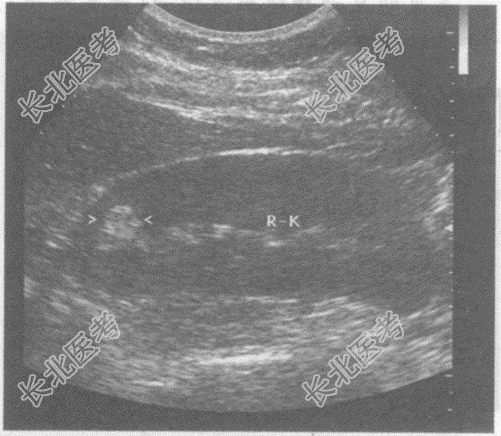

- 单项选择题临床资料:女, 27岁,常规体检。

超声综合描述: 右肾形态、大小正常,上极实质部可见1.2cm×1.2cm圆形增强回声区, 边界清晰,形态规则, 内回声欠均。

超声提示: A、右肾错构瘤

B、右肾癌

C、右肾脓肿

D、右肾肥大肾柱

E、右肾上腺囊肿